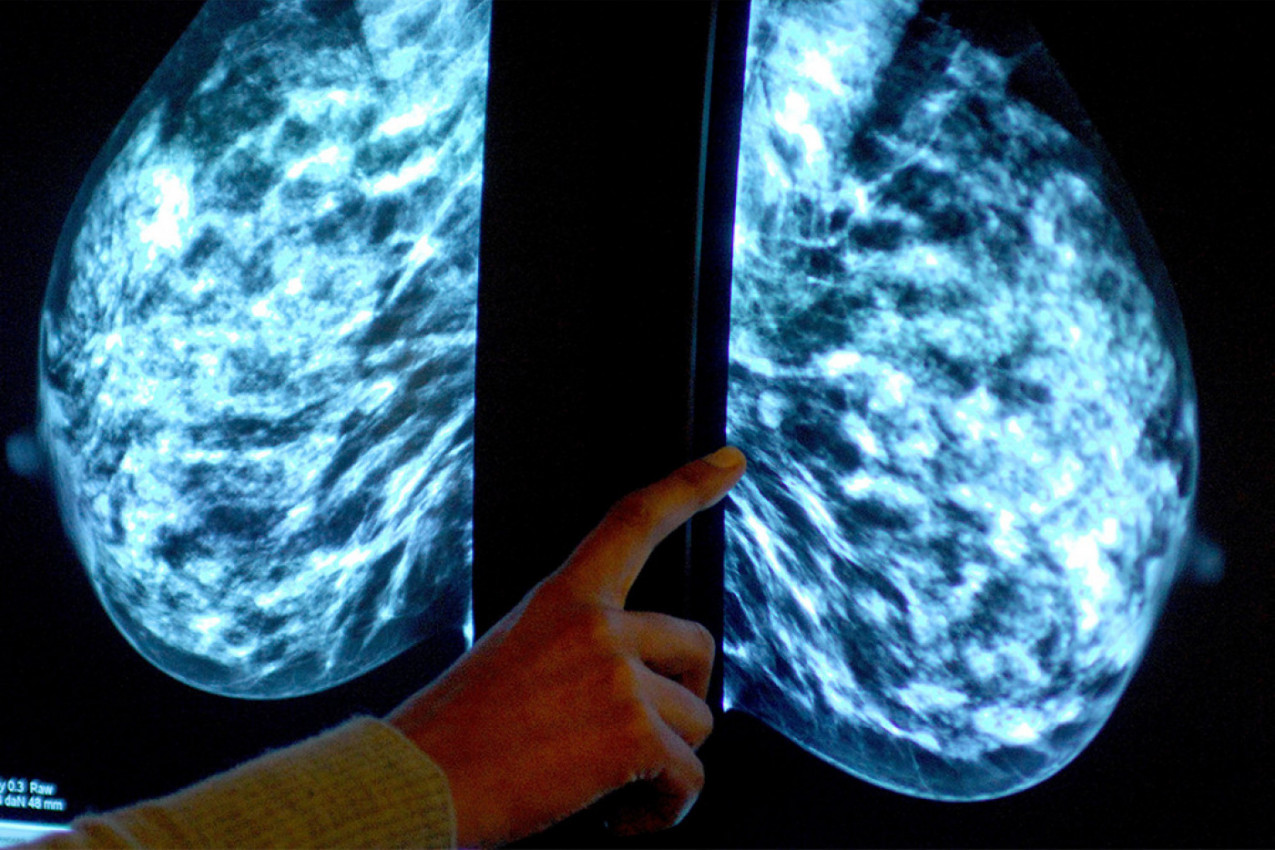

Inače, ultrazvuk i CT skener pokazali su blago otečene limfne čvorove oko pazuha žene i guste krvne sudove, za koje veruju da je od uvećanog tkiva dojke, piše Dejli Mejl (Daily Mail).